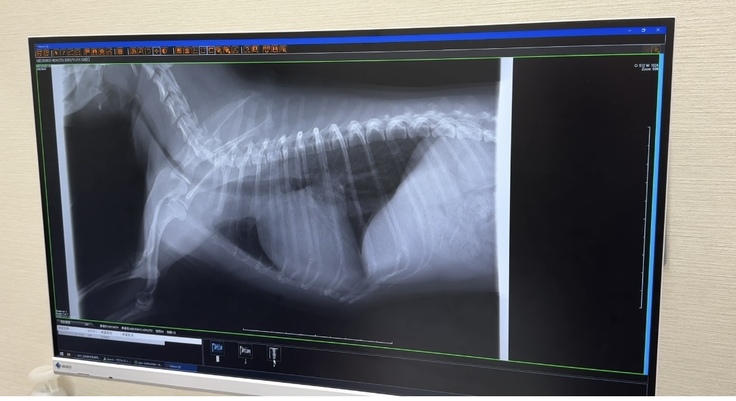

▽レントゲン写真

心臓が大きくなってしまってます

(通常の大きさが1.6以下なのですが、ほくとの場合2になってしまってます)